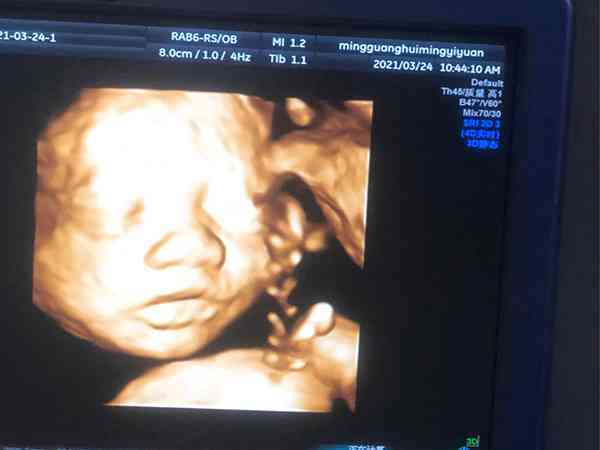

我剛剛懷孕6個月,這是我的二胎了。老大是個男孩子,所以我和老公決定給他生個妹妹。前幾天做四維檢查,通過檢查結果我和老公都很開心,因為顯示是個女孩子。但是我看網上還有人說,有許多人六個月的四維彩超到最後卻生出了男孩,所以想了解一下6個月的四維是女孩結果生了男孩的例項多嗎?6個月四維女孩卻生了男孩的例項還是有的,但是不是特別多。因為現在四維彩超的準確率很高,且懷孕6個月後基本胎兒的生殖器官已經發育好了,大部分情況下是不會出現誤判的。不過現在我國禁止提前告知胎兒性別,因此醫生一般會避開生殖器檢查,而四維彩超的資料來看胎兒性別是沒有科學依據的,因此如果懷孕6個月四維是女孩,但生下來是男孩的情況是存在的。

四維彩超可以清晰看見寶寶的狀態,是孕期胎兒排畸的重要檢查手段,懷孕6個月的四維準確率一般可以達到80%左右了,但還是有誤判的可能,一般是因為以下幾種原因: